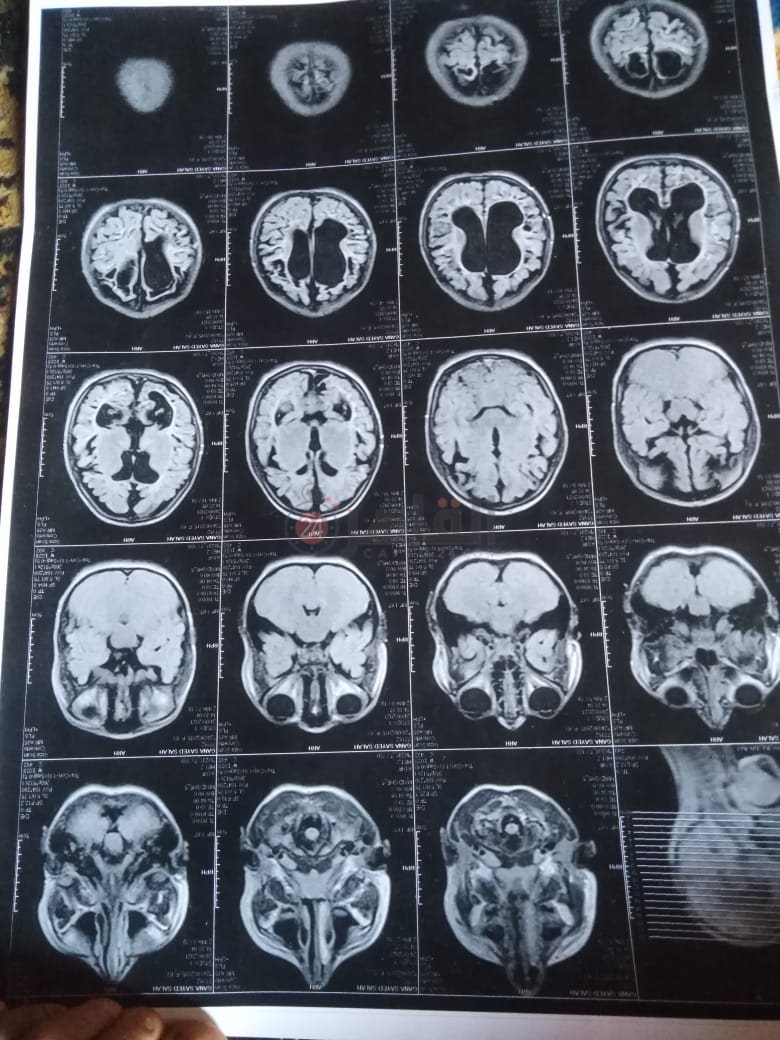

من جانبه، قال صلاح سيد، والد الطفلة جنى صلاح، إن ابنته تعاني من ضمور في المخ منذ ولادتها، نتيجة خطأ طبي، أدى إلى نقص كبير في الأكسجين لديها.

وأضاف في تصريحات خاصة لـ "القاهرة 24": "جنى تبلغ من العمر 6 سنوات، لا تستطيع المشي أو الوقوف على قدميها، نتيجة إصابتها بضمور في المخ منذ ولادتها".

وتابع: "مكنتش بتتحرك خالص، وجسمها طري، روحت كشفت عليها، وعملت أشعة وتحاليل كتير، أتأكدنا إصابتها بضمور في المخ"، مضيفًا:" مش بتعرف تأكل احنا اللي بنأكلها، هي عقلها كويس لكن مش بتتحرك ولا تتكلم".